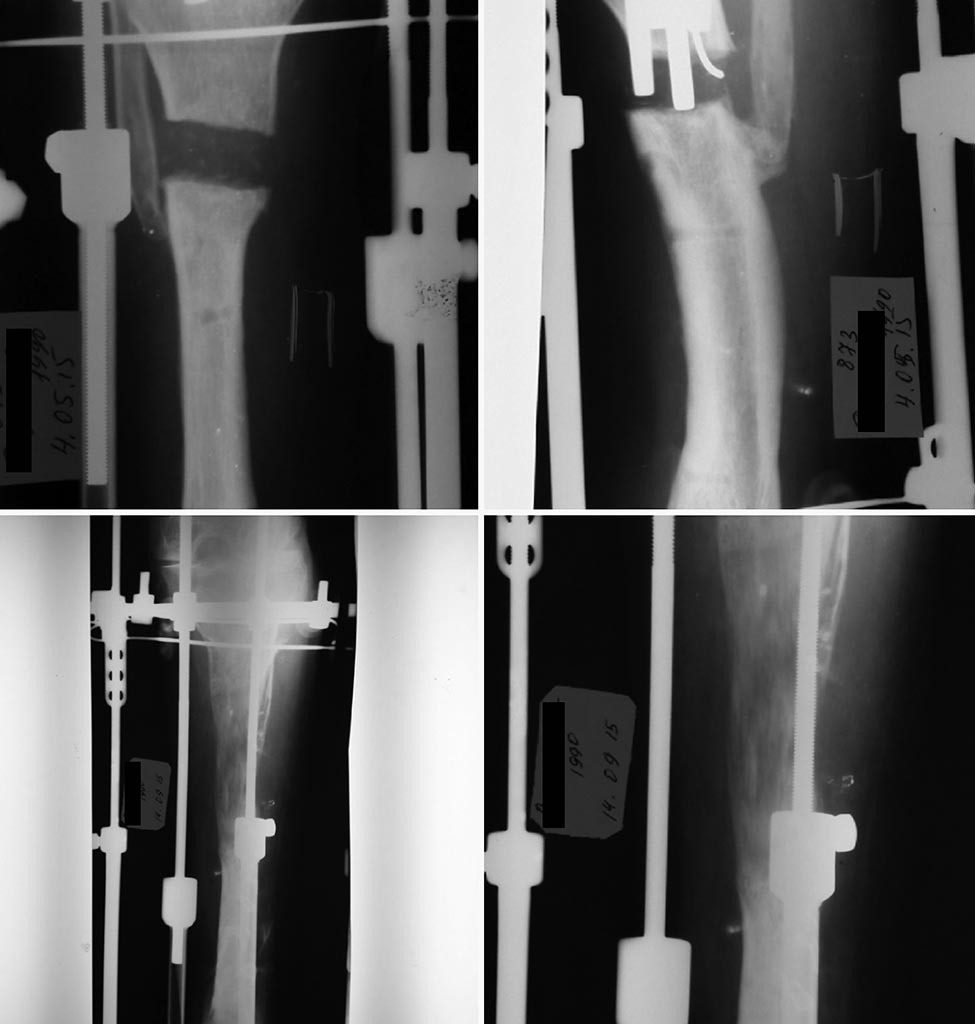

Больная 27 лет. В детстве перенесла острый гематогенный остеомиелит правой голени. Впоследствии образовался пателло-феморальный синостоз и отставание в развитии костей голени, варусная деформация голеностопного сустава за счет развития м/б кости. Укорочение голени было на 14 см.

В конце 2014 года в нашем отделении поэтапно произведено: корригирующая надлодыжечная остеотомия, фиксация накостной пластиной. Далее через 7 мес. удаление фиксатора, кортикотомия верхней трети большеберцовой кости с наложением аппарата Илизарова, постепенная дистракция аппаратом до 7см.

Дистракцию остановили в связи с появлением болевого синдрома. Держали в аппарате 3 мес. после приостановки дистракции.

По настоянию пациентки и родителей (девушку выдавали замуж) аппарат снят, наложен гипсовый сапог с каблуком. После этого пациентка исчезла из поля нашего зрения (живёт в отдаленном районе). Гипсовая повязка снята в поликлинике по месту жительства (на какой срок – не известно).

Недавно больная объявилась с жалобами на боли в области голени. При осмотре выраженное укорочение правой голени, деформация по типу рекурвации в в/3 голени, эквинусная деформация стопы (компенсаторная). Движения в коленном суставе - разгибание полное, сгибание 20º. На р-грамме ложный сустав в/3 большеберцовой кости с рекурвацией, пателло-феморальный синостоз.

В плане лечения мнения разделились. Планируем произвести резекцию ложного сустава, вскрытие костно-мозгового канала с наложением аппарата Илизарова, постепенное исправление деформации, выведение стопы в правильное положение. Далее желаем произвести БИОС большеберцовой кости.

Смущает синостоз надколенника и разгибательная установка коленного сустава. Как быть в таких случаях? Можно ли сбить надколенник с бедренной кости, поперечно распилить, произвести БИОС из этого доступа, а затем синтезировать надколенник по Веберу. Какие будут мысли на этот счет? Буду признателен любому мнению. Надеюсь на помощь сообщества.